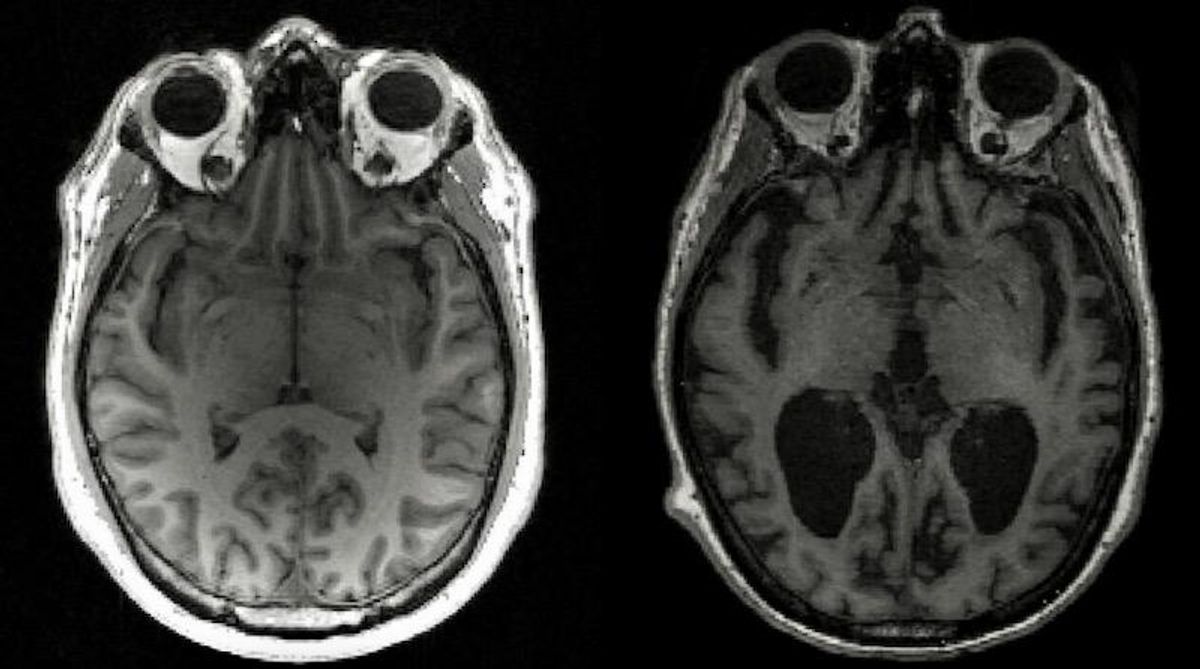

In Alzheimer's disease, tau and another protein called amyloid-beta build up into tangles and plaques -- known together as aggregates -- that cause brain cells to die and lead to brain shrinkage.

This in turn results in memory loss, personality changes and inability to carry out daily functions associated with the condition, which affects 44 million people globally.